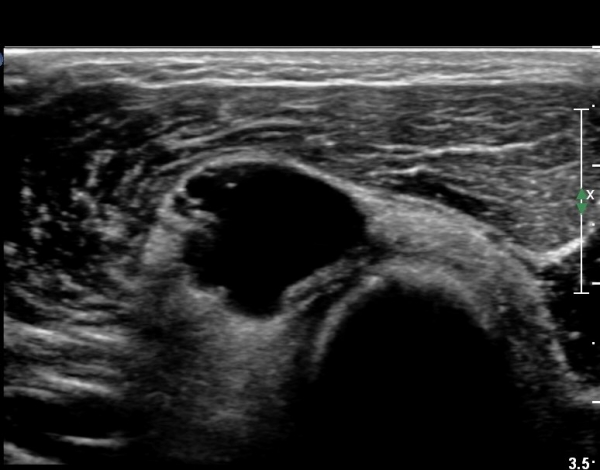

ŽÃÊÀÚ¸¦ ȸ¿Ü±Ù ºÎÀ§±îÁö À̵¿ÇÏ´Ï ³¶Á¾Àº °í³ªÂûµÇÁö ¾Ê°í µÎ ȸ¿Ü±Ù »çÀÌ¿¡ Àִ  Èİñ°£½Å°æ

ºÎÁ¾ÀÌ °üÂûµÈ´Ù(»çÁø 4).

Èİñ°£½Å°æ Á¾´Ü¸é°Ë»ç¿¡¼­ ³¶Á¾°ú ÀÎÁ¢ÇÏ¿©  À§Ä¡ÇÑ Èİñ°£½Å°æÀÇ ºÎÁ¾ÀÌ °üÂûµÈ´Ù(»çÁø 5, 6).